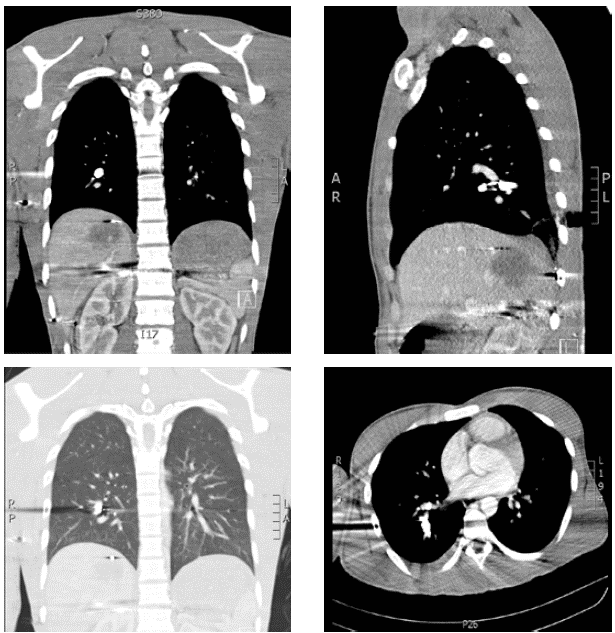

Se practicó una tomografía toracoabdominal con contraste que mostró neumomediastino: proyectil en la arteria pulmonar del lóbulo inferior derecho, con signos de embolia pulmonar aguda en sus ramas distales, proyectil en los tejidos blandos de la pared torácica posterior derecha asociado con laceración y contusión en la base pulmonar; no había neumotórax ni hemotórax; además, se apreció una laceración hepática profunda con compromiso del segmento VII, con signos de sangrado activo y hematoma subcap-sular hepático contenido (figura 1). Se ordenó una arteriografía que no demostró sangrado activo; también, se practicó angiotomografía y arteriografía del miembro superior derecho y no se encontró sangrado ni lesión vascular.